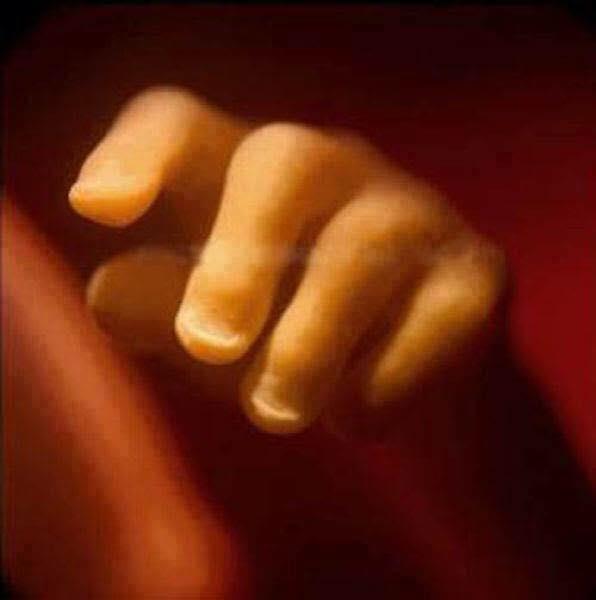

19 semanas, já é possível ver as unhas

20 semanas, medindo aproximadamente 20 centímetros